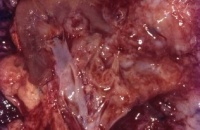

Die karzinomatöse Entartung persistierender metanephrogener Stammzellen (Blastem) auf der Grundlage einer zytogenetischen Deletion auf dem kurzen Arm des Chromosoms 11 in der p13-Region (Wilmstumor1-Gen) bzw. Mutation auf 11p15,5 (WT2-Gen) führen zur Entwicklung eines Wilmstumors. Durch die Pluripotenz des Blastems können vielfältige epitheliale und mesenchymale Zell- und Gewebskomponenten nebeneinander histologisch nachweisbar sein, wie beispielsweise alle in der Niere vorkommenden Gewebe, aber auch Skelettmuskel-, Knorpel- und Schleimzellen. Die Tumoren können zystisch aufgebaut sein. Anaplastische Tumoranteile (Kernhyperchromasie, hyperdiploide Mitosen, mehr als dreifach vergrößerte Zellkerne) treten in ca. 5% der Fälle auf und sind als prognostisch ungünstiges Kriterium zu werten. Die Tumorzellen können - genau wie beim Nierenzellkarzinom - durch Aggregation in den Blutgefäßen Tumorthromben bilden (Abbildung 1c). Wilmstumoren metastasieren nach medial in die Lymphknoten und hämatogen in die Lunge. Vereinzelt finden sich ZNS-, Leber- und Skelettmetastasen.

Auf der Schnittfläche ist der Tumor von gelbbrauner bis grauer Farbe mit einzelnen Einblutungen. Zystische Anteile und Nekrosen kommen vor sowie oberflächlich glatte, knotenförmige Strukturen, ähnlich einem Rhabdomyosarkom (Abbildung 1a-d).